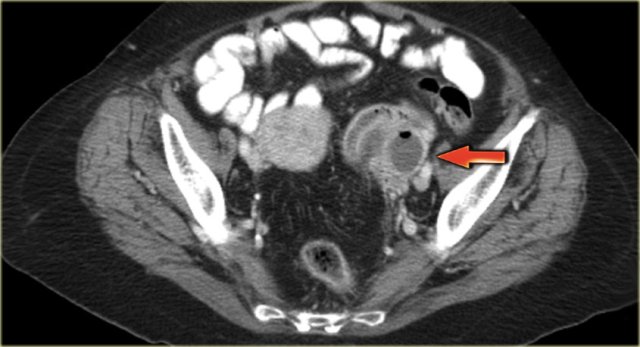

Ultrasound shows a complex solid-cystic mass in the left ovary, and another, very large complex solid-cystic mass in the right hemi-pelvis.

CT of the same patient shows a complex solid-cystic mass with thick, enhancing septations in the right ovary.

These findings are very suspicious for a malignant cystic neoplams.

There is also bilateral lymphadenopathy (arrows).

Pathology showed a serous ovarian cystadenocarcinoma.

This is the most common type of ovarian cancer.